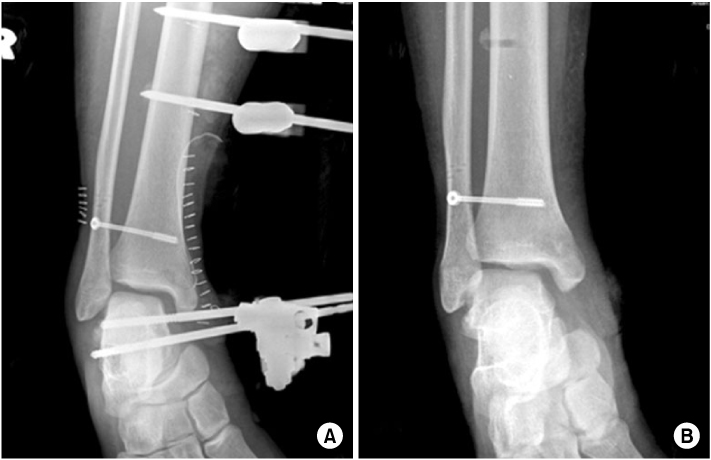

Fig. 4

(A) For initial treatment, open reduction and external fixation of ankle joint was done and a syndesmotic screw was inserted at other clinic.

(B) Follow-up X-ray with the external fixator removed 2 months later.

Fig. 4 (A) For initial treatment, open reduction and external fixation of ankle joint was done and a syndesmotic screw was inserted at other clinic. (B) Follow-up X-ray with the external fixator removed 2 months later.